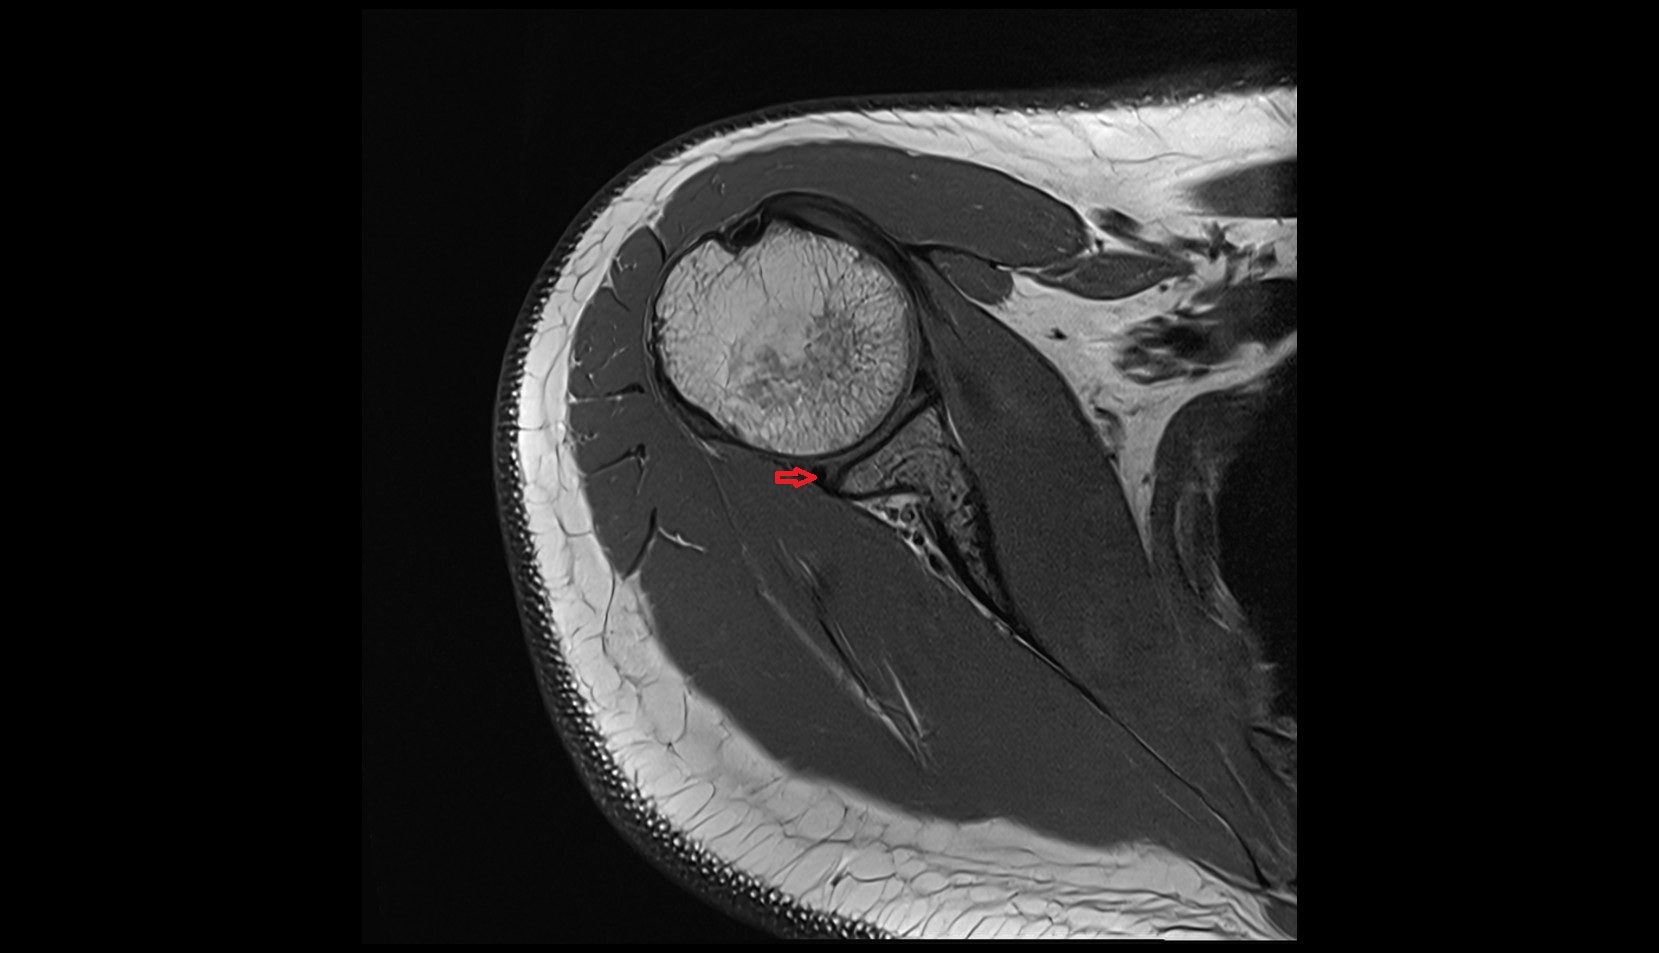

- Shoulder joint (glenohumeral joint)

- Glenoid labrum

- Supraspinatus tendon

- Infraspinatus tendon

- Subscapularis tendon